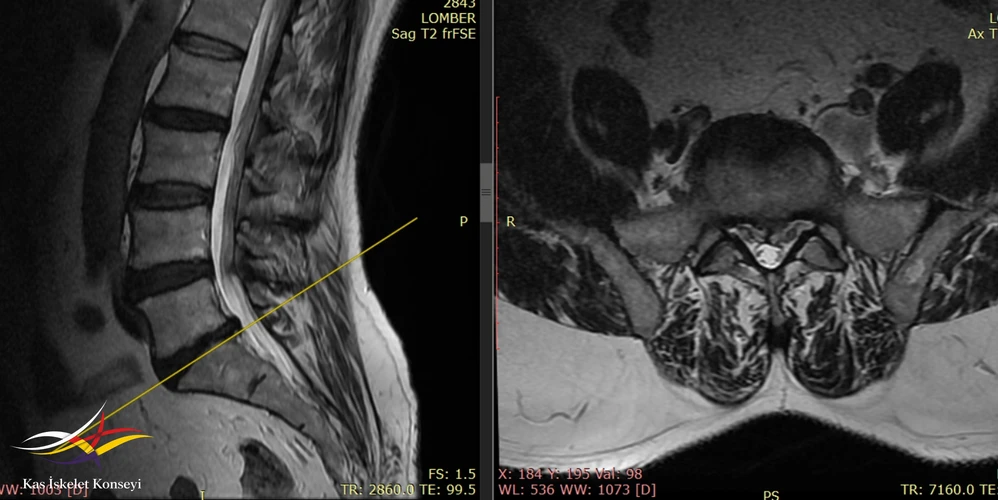

İncelemeler: Lomber MRG de L5-S1 santral disk hernisi mevcuttu. Solda korpus ön komşuluğunda iliak ven genişlemiş görünüyordu (Resim). Yapılmış olan EMG incelemesinde solda "L3-L5 spinal ganglion proksimalinde tutulum" rapor edilmişti.

Resim 3. Lomber MRG'de L5-S1 disk hernisi görülmekte. Sol iliak ve korpus ön komşuluğunda dilate görünümde.

Resim 4. Lomber MRG, daha kaudal kesitte sol iiak arter ve ven ilişkisi görülmekte.